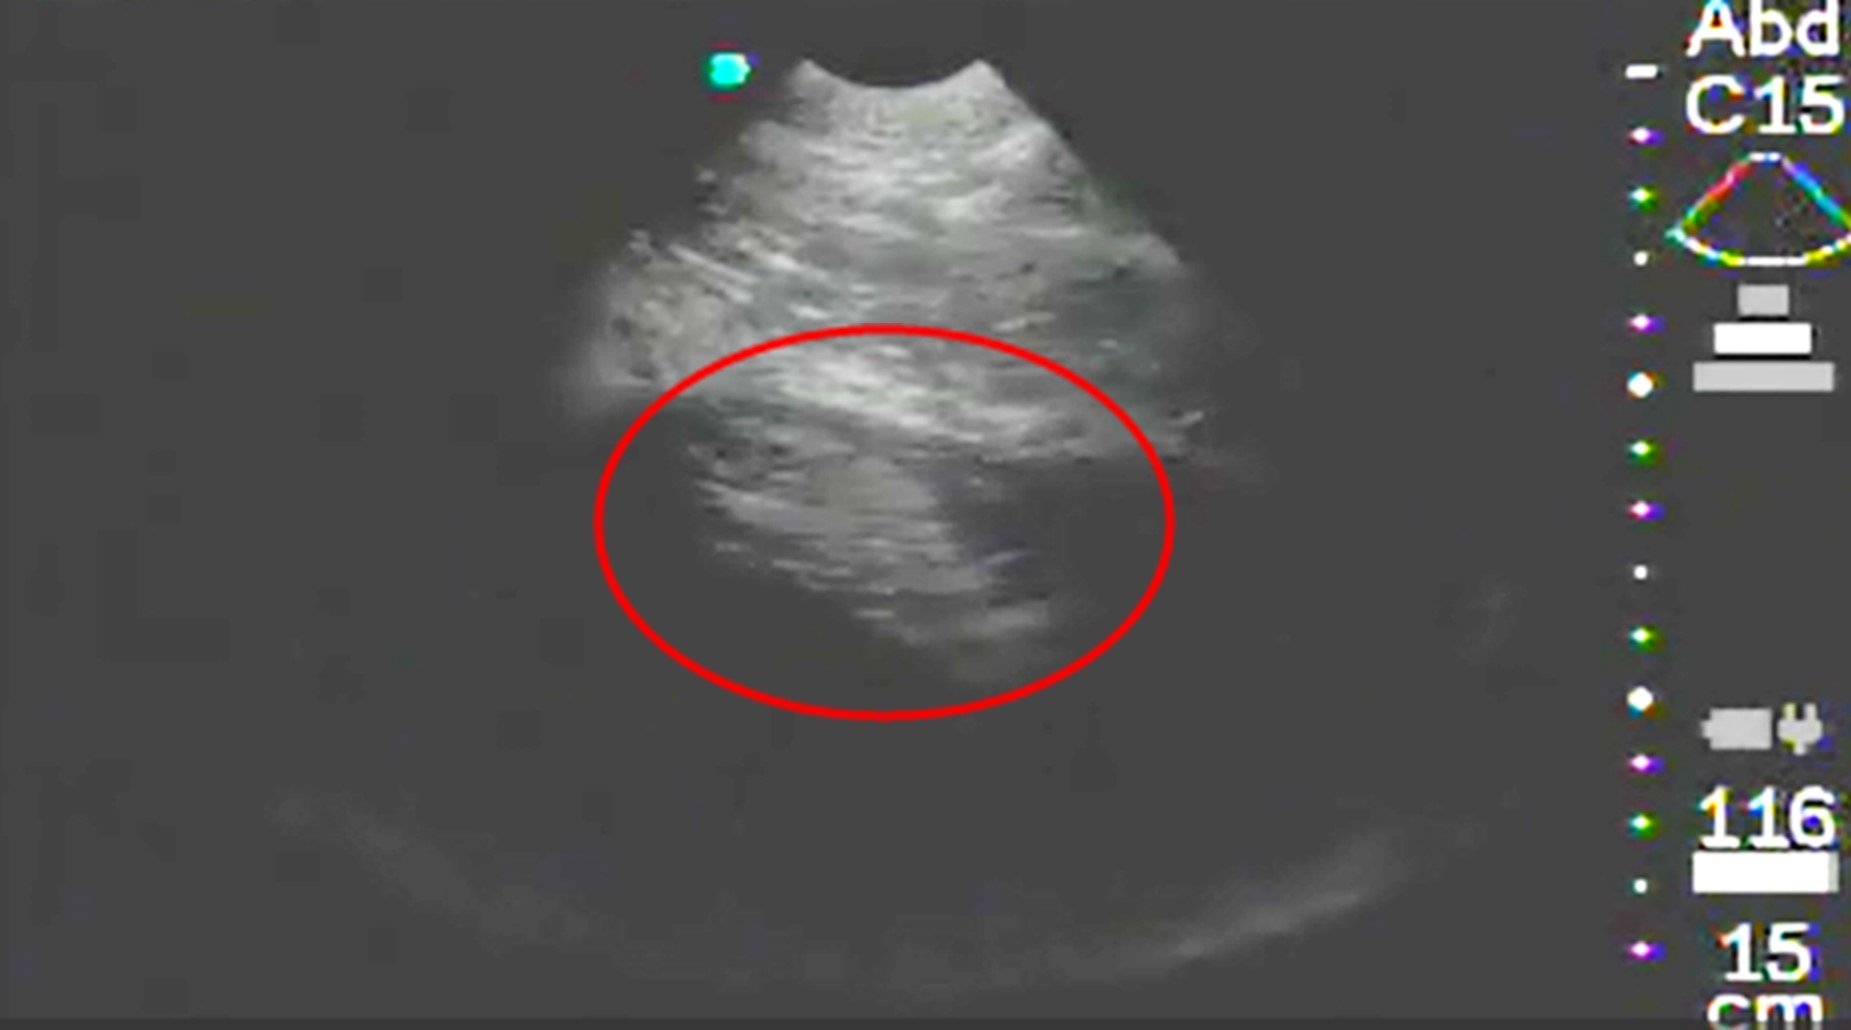

さらに令和6年(2024年)7月29日に、超音波診断装置(エコー)による検査を行なったところ、胎仔は確認できませんでしたが、羊水を容れた子宮らしきものが確認できました。改めて8月14日に超音波診断装置(エコー)による検査を行なったところ、左下腹部に子宮の羊水内の胎仔が認められたため、妊娠の確定診断としました。

エコー画像(令和6年(2024年)8月14日撮影)

〇の中に見える白い部分が羊水に浮かぶ胎仔。画像上部が腹壁側。